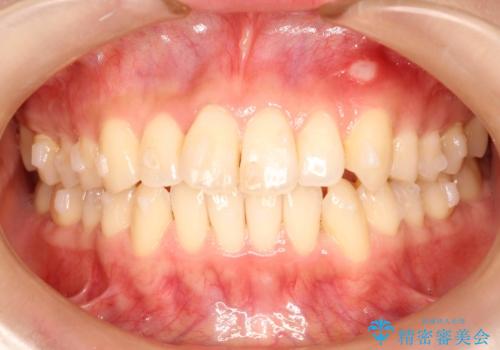

前歯のガタガタをインビザラインで目立たず矯正

- 目立たずに前歯を矯正したいとのことで来院されました。

歯と歯の間にわずかに隙間を作りスペースを確保し、インビザラインにて矯正を行うこととなりました。

前歯の微調整に少し時間がかかりましたが、整った歯並びにすることができました。